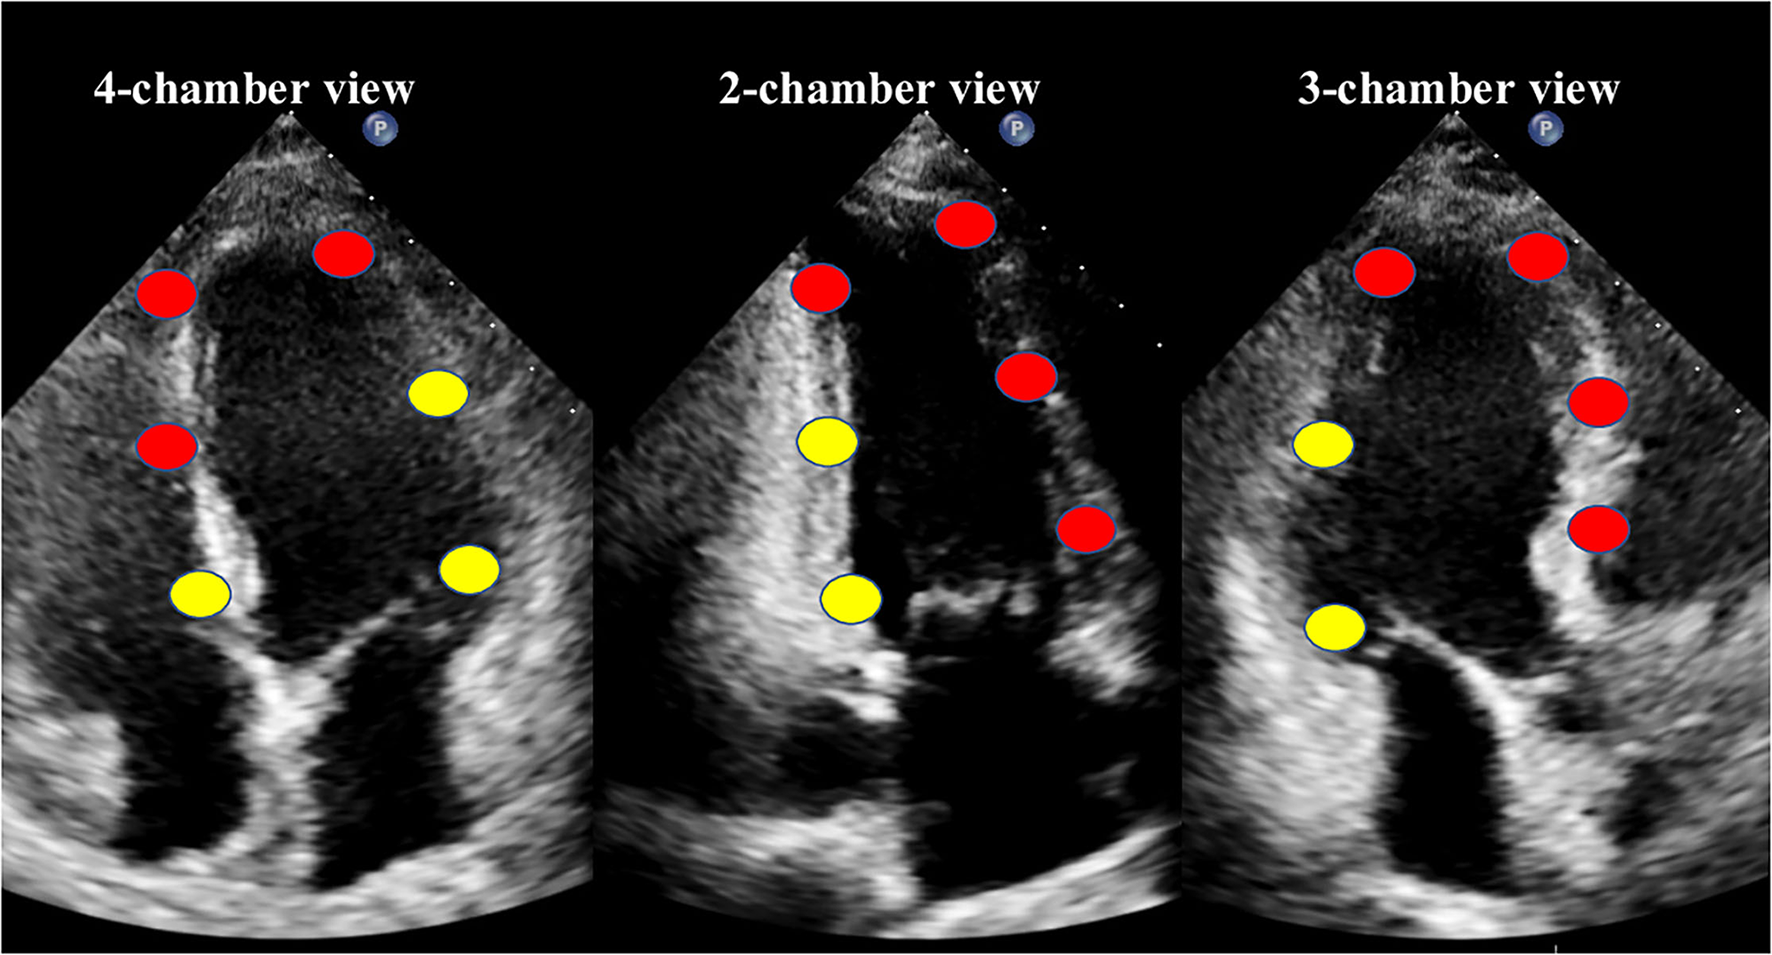

The values of culprit regional MW [including work index-LAD (WI-LAD), constructive work-LAD (CW-LAD), wasted work-LAD (WW-LAD), and work efficiency-LAD (WE-LAD)] and non-culprit regional MW (including WI-nonLAD, CW-nonLAD, WW-nonLAD, and WE-nonLAD) were obtained as the average of the segments belonging to the LAD or non-LAD territory (11 segments for the LAD, and 7 segments for the non-LAD; Figure 1) (18). The absolute differences of the MW indices were calculated as the values of non-culprit regional MW minus the values of culprit regional MW and noted as delta-WI, delta-CW, delta-WW, and delta-WE.

Figure 1

The18-segment model for myocardial work analysis. Red dots indicate the segments of the left anterior descending coronary artery (LAD) territory, while yellow dots indicate the non-LAD territory.